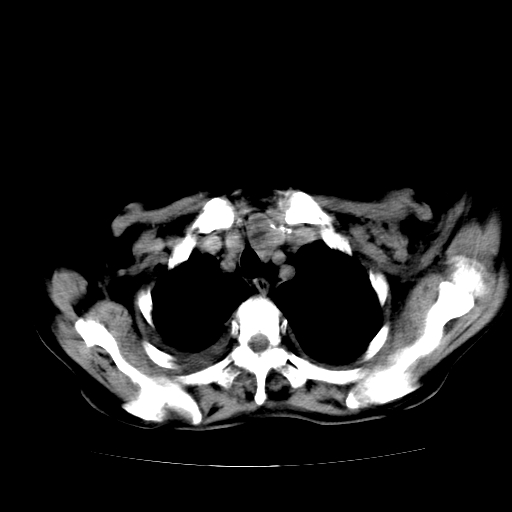

标题: CT17152:女70Y乳腺CA

女70y乳腺ca(针吸活检)

多部位转移瘤的诊断可以肯定,我的疑问是:双肺对称高密度影及胸水是否为心衰肺水肿,病人体虚弱,不好意思图象传的乱![em9]